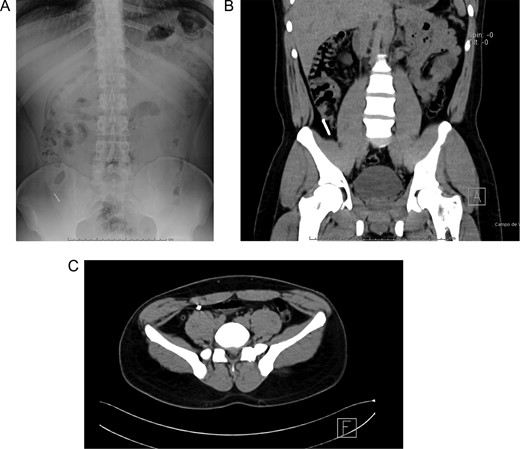

Patient is a 27-year-old male without past medical history. During his annual routine medical examination, an abdominal X-ray was requested. A metallic foreign body (30 mm nail) was discovered in his lower right abdomen (Fig. 1A). With these findings, he was transferred to our hospital. On arrival, he was completely asymptomatic, and he had no recollection of having swallowed the nail. Abdominal examination was unremarkable, and he had no evidence of any surgical scars. With these findings, a contrast-enhanced abdominal computed tomography (CT) revealed the presence of a 30 mm metal nail inside his appendix (Fig. 2A). The appendix had an outer diameter of 5 mm and was surrounded by homogeneous, non-inflamed fat and contained intraluminal air (Fig. 3A). A colonoscopy was requested to assess the cecum to try to remove the foreign body, however, after reaching the cecum and the appendix the nail could not be found (Fig. 1B). An intraoperative abdominal x-ray was needed, which confirmed the presence of the nail in the appendix (Fig. 2B).

(A) Abdominal X-ray with a radiopaque metallic foreign body. (B) Abdominal CT, the metallic foreign body is lodged in the appendix. (C) Abdominal CT, the appendix is surrounded by homogeneous non-inflamed fat and contains intraluminal air.

(A) Colonoscopy, the appendiceal orifice is seen without the foreign object. (B) Intraoperative abdominal x-ray confirming the presence of the nail in the appendix. (C) Appendix during surgery.

In this context, a surgical approach was needed to assess the appendix and the cecum wall. After a Rocky-Davis incision, the appendix was exposed and an object of hard consistency was found at its tip (Fig. 3B). The surgical decision was straightforward, the appendix was resected, and the surgery was completed without complications (Fig. 1C).

After this, the appendix was dissected and a 30 mm nail was found inside its lumen (Fig. 2C and Supplementary Video).